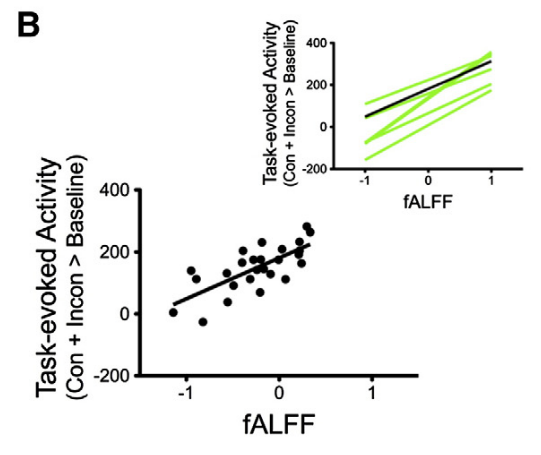

Methods: effect of CVR on fMRI

Results were thresholded at \(p<0.05\) after controlling for false discovery rate³

(then at \(p<0.001\) uncorrected)

1. Chen et al. 2013 (Neuroimage); 2. Golestani et al. 2016 (NeuroImage); 3. Benjamini et al. 2006 (Biometrika)

We used 3dLMEr¹ to set up the following LME models voxelwise (R syntax):

- \(RSF \sim cvr + (cvr|session) + (cvr|subject)\)

- \(tIA \sim RSF + (RSF|session) + (RSF|subject)\)

- \(tIA \sim cvr + (cvr|session) + (cvr|subject)\)

We used the first model considering the average GM value of RSF and CVR²

- \(RSF \sim cvr + (cvr|session) + (cvr|subject)\)

- \(tIA \sim RSF + (RSF|session) + (RSF|subject)\)

- \(tIA \sim cvr + (cvr|session) + (cvr|subject)\)

Results: CVR, RSF, and tasks

The relationship between CVR, RS fluctuations, and tIA

might be highly subject specific

or absent altogether.

- We did not observe a statistically significant effect of CVR on RS fluctuations, or of CVR and RS fluctuations on task induced activity, most probably due to the high variability between subjects

The failure of generalisation of previous observations might be related to different methods, but whether this is related to a better denoising and signal quality or to a possibly non optimal setting (e.g. compared to gas challenges) is uncertain

A different statistical perspective (i.e. Bayesian) is required to exclude any relationship between CVR and RS fluctuations, and further analyses are required to improve the agreement between CVR and RS fluctuations